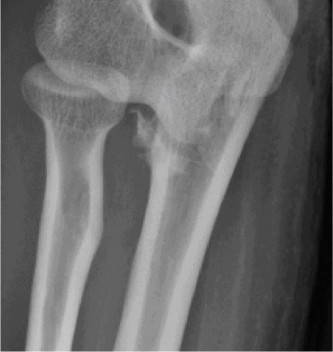

A 54-year-old male presented to the ED with left elbow pain after sustaining an injury in a low speed motor vehicle accident. He denied any other injuries. On examination, he had no open injuries and was neurovascularly intact. He had gross deformity about the elbow. His images are below (Figs. 2–89 to 2–92).

Figure 2–92 Pre- and post-reduction films showing complex elbow dislocation, coronoid fracture.

The correct answer is (C). Posteromedial complex elbow dislocation. This injury is proposed to result from axial load combined with posteromedial rotation, varus force, and elbow flexion. This is opposed to the more frequently seen posterolateral dislocation. There is a fracture of the coronoid, which is typical for this type of injury.

The correct answer is (A). Coronoid process fracture (see Fig. 2–93). The medial trochlea is thought to fracture the anteromedial facet of the coronoid allowing the elbow to dislocate. The lateral collateral ligament (LCL) ligamentous complex is also torn with this type of injury however the radial head often remains intact. This is in contrast to posterolateral elbow dislocations in which the radial head is the most commonly fractured bone, followed by the coronoid.